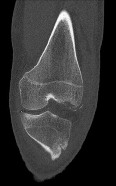

Question 3:

A 22-year-old soccer player sustains a twisting injury to his knee during a match. Radiographs reveal a small elliptical bone fragment adjacent to the lateral tibial plateau (Segond fracture). Based on this radiographic finding, which physical exam maneuver is most likely to be positive in this patient?

Correct Answer: Positive pivot shift test

Explanation:

A Segond fracture is an avulsion fracture of the anterolateral ligament (ALL) and lateral capsule from the lateral tibial plateau. It is highly pathognomonic (up to 75-100% predictive value) for an anterior cruciate ligament (ACL) tear. The pivot shift test is the most specific physical examination finding for assessing rotational laxity associated with an ACL-deficient knee.